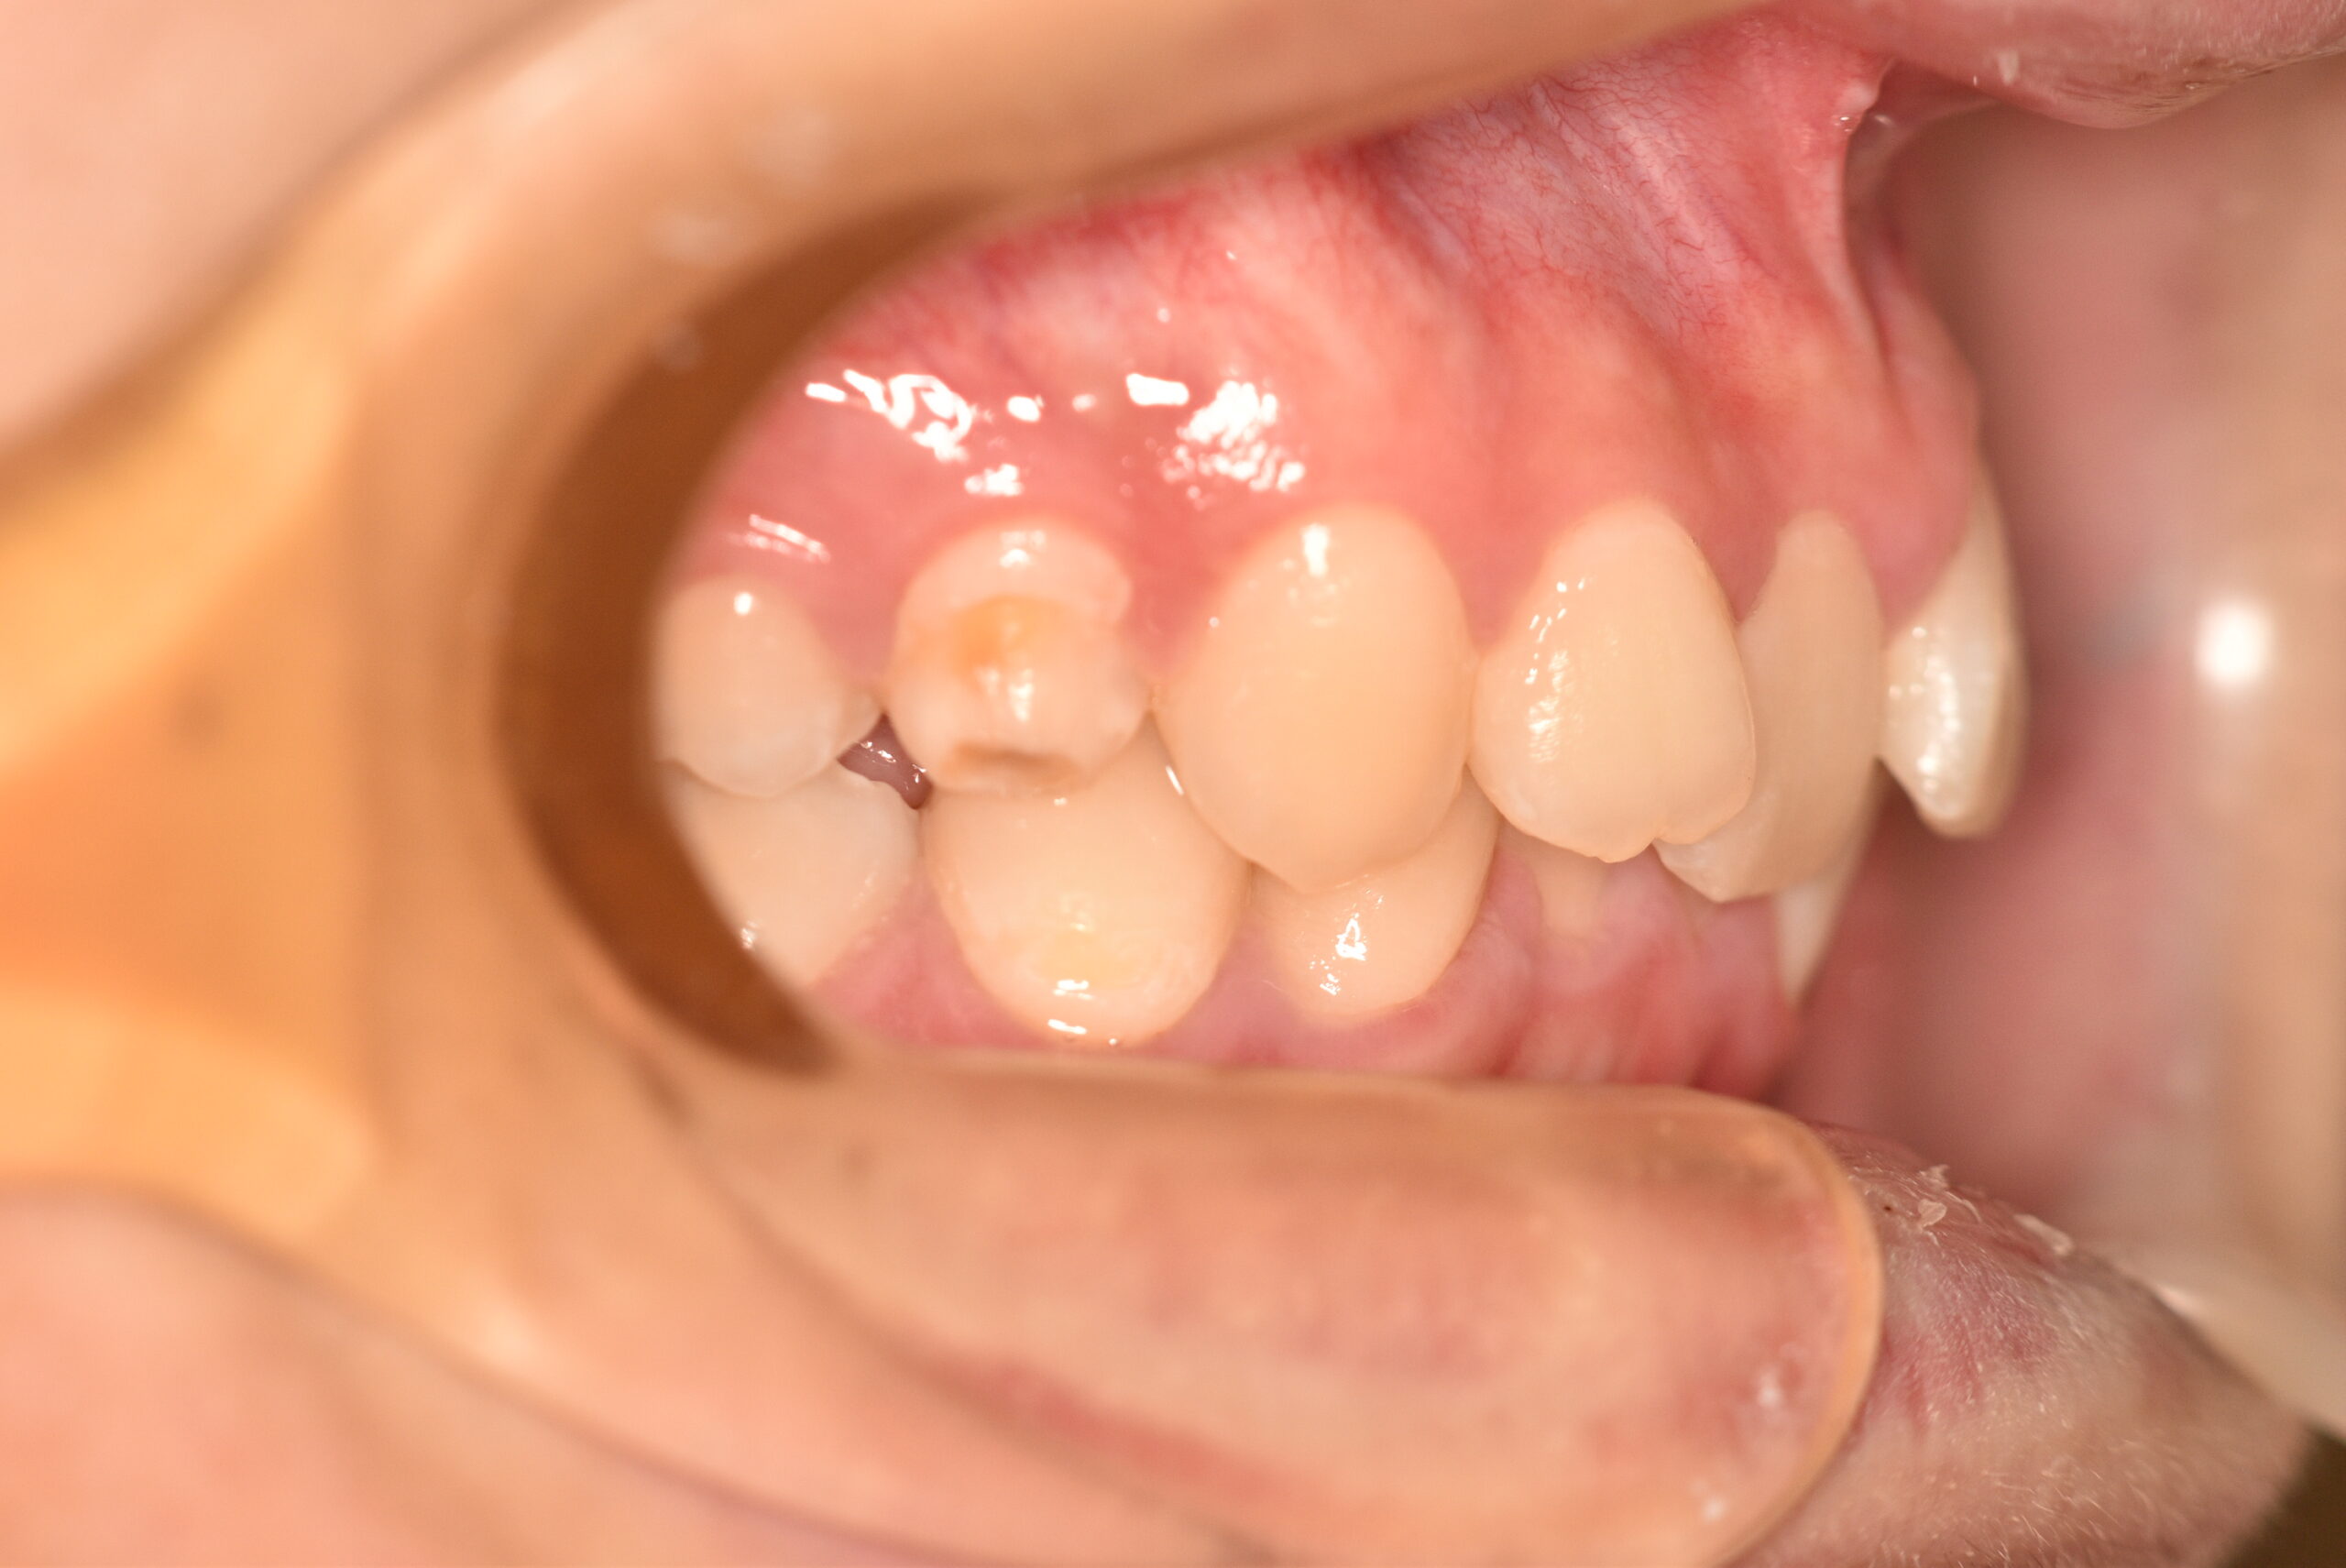

| 治療内容の詳細 | 初診時16歳の男性で、歯のがたつき、かみ合わせを気にされ来院しました。 検査の結果、アングルⅡ級2類不正咬合と診断しました。 治療としては、非抜歯の上、セルフライゲーションブラケット装置(デーモンシステム)で配列を行いました。 同時に顎間ゴムにて咬合関係の改善を行いました。 治療期間は、1年6ヶ月でした。 |